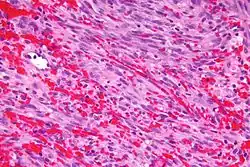

KS lesions contain tumor cells with a characteristic abnormal elongated shape, called spindle cells. The most typical feature of Kaposi sarcoma is the presence of spindle cells forming slits containing red blood cells. Mitotic activity is only moderate and pleomorphism is usually absent.[31] The tumor is highly vascular, containing abnormally dense and irregular blood vessels, which leak red blood cells into the surrounding tissue and give the tumor its dark color. Inflammation around the tumor may produce swelling and pain. Variously sized PAS positive hyaline bodies are often seen in the cytoplasm or sometimes extracellularly.

The spindle cells of Kaposi sarcoma differentiate toward endothelial cells, probably of lymph vessel rather than blood vessel origin.[32] The consistent immunoreactivity for podoplanin supports the lymphatic nature of the lesion.

Micrograph of a Kaposi sarcoma showing the characteristic spindle cells, high vascularity, and intracellular hyaline globs. H&E stain.

Micrograph of a Kaposi sarcoma showing the characteristic spindle cells, high vascularity, and intracellular hyaline globs. H&E stain. -